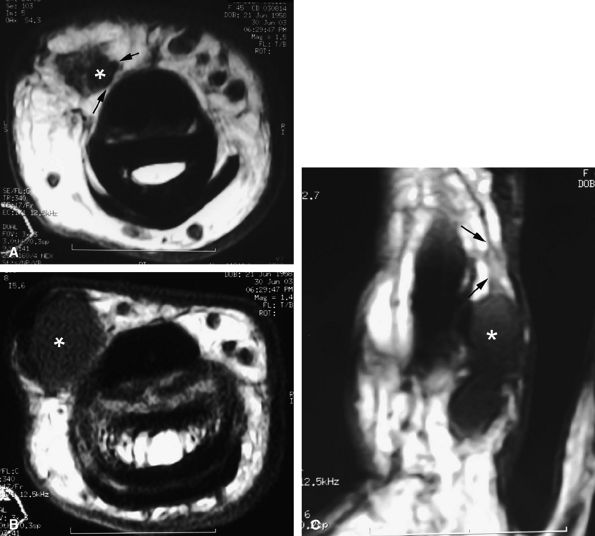

FIGURE 11.34 ● Complete rupture of the central slip of the extensor tendon on sagittal (A) and axial post-enhanced T1-weighted images at the level of the PIP joint space (B) and the distal third of the proximal phalanx (C). There is distal avulsion of the central slip with a tendon gap (arrows) and limited retraction. The proximal end is thickened and shows signal heterogeneity (asterisk).

|